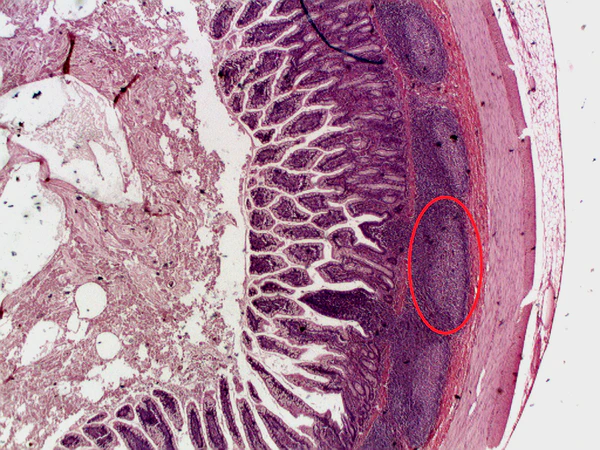

Пейеровы бляшки

Пейеровы бляшки (или агрегированные лимфоидные узелки) (лат. noduli lymphoidei aggregati) — это скопления (агрегаты) солитарных лимфатических фолликулов в дистальном отделе тонкой и проксимальном отделе толстой кишки. Составляющие пейеровы бляшки солитарные фолликулы имеют вид беловатых возвышений плоской, линзо- или шарообразной, реже — заостренной формы. Форма фолликулов определяет положение слизистой оболочки в этой области стенки кишки (может возвышаться над фолликулом или образовать углубление).[1] Пейеровы бляшки также называют тканевым барьером между патогенами и внутренней средой организма.[2] Они названы в честь швейцарского анатома XVII века Иоганна Конрада Пейера

Основная масса пейеровых бляшек локализуется в подвздошной кишке, особенно в самом нижнем его отделе по всей окружности стенки кишки. Но чаще они находятся на стороне, противоположной месту приклепления брыжейки. Количество пейеровых бляшек у большинства людей равняется 20 — 30. С возрастом их число увеличивается. Каждая пейерова бляшка состоит в среднем из 10 — 25 солитарных фолликулов (возможны комбинации от 20 до 400 и более). В верхнем отделе кишки пейеровы бляшки имеют круглую форму, в конце — овальную или эллипсоидную. Из подслизистого слоя они немного выступают над поверхностью слизистой. При осмотре слизистой кишки пейеровы бляшки имеют вид овальных пластинок длиной 2 — 10 см, шириной — 0,12 — 1,2 см. Продольный диаметр пейеровых бляшек совпадает с продольной осью кишки. Величина бляшки с возрастом увеличивается. На слизистой, покрывающей верхушки лимфатических фолликулов пейеровых бляшек, ворсинки сидят очень редко или совсем отсутствуют. Нередко слизистая над ними даже слегка вдавливается, в результате чего образуются маленькие ямки.